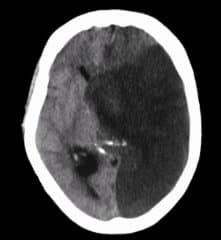

Midline brain shift may be evident in neuroimaging such as CT scanning. The sign is considered ominous because it is commonly associated with a distortion of the brain stem that can cause serious dysfunction evidenced by abnormal posturing and failure of the pupils to constrict in response to light.

Doctors detect midline shifts using a variety of methods. The most prominent measurement is done by a computed tomography (CT) scan and the CT Gold Standard is the standardized operating procedure for detecting MLS.

Since the midline shift is often easily visible with a CT scan, the high precision of Magnetic Resonance Imaging (MRI) is not necessary, but can be used with equally adequate results.

The brain is naturally balanced between the left and the right hemispheres. On a computed tomography (CT) scan that looks down at the brain from the top of the head, there is a groove that runs between both sides of the brain that is midline to the body.

The spinal cord emerges at the middle base of the brain and continues down the center of the back. A midline shift occurs when something pushes this natural centerline of the brain to the right or to the left. It is a concerning sign after head trauma.